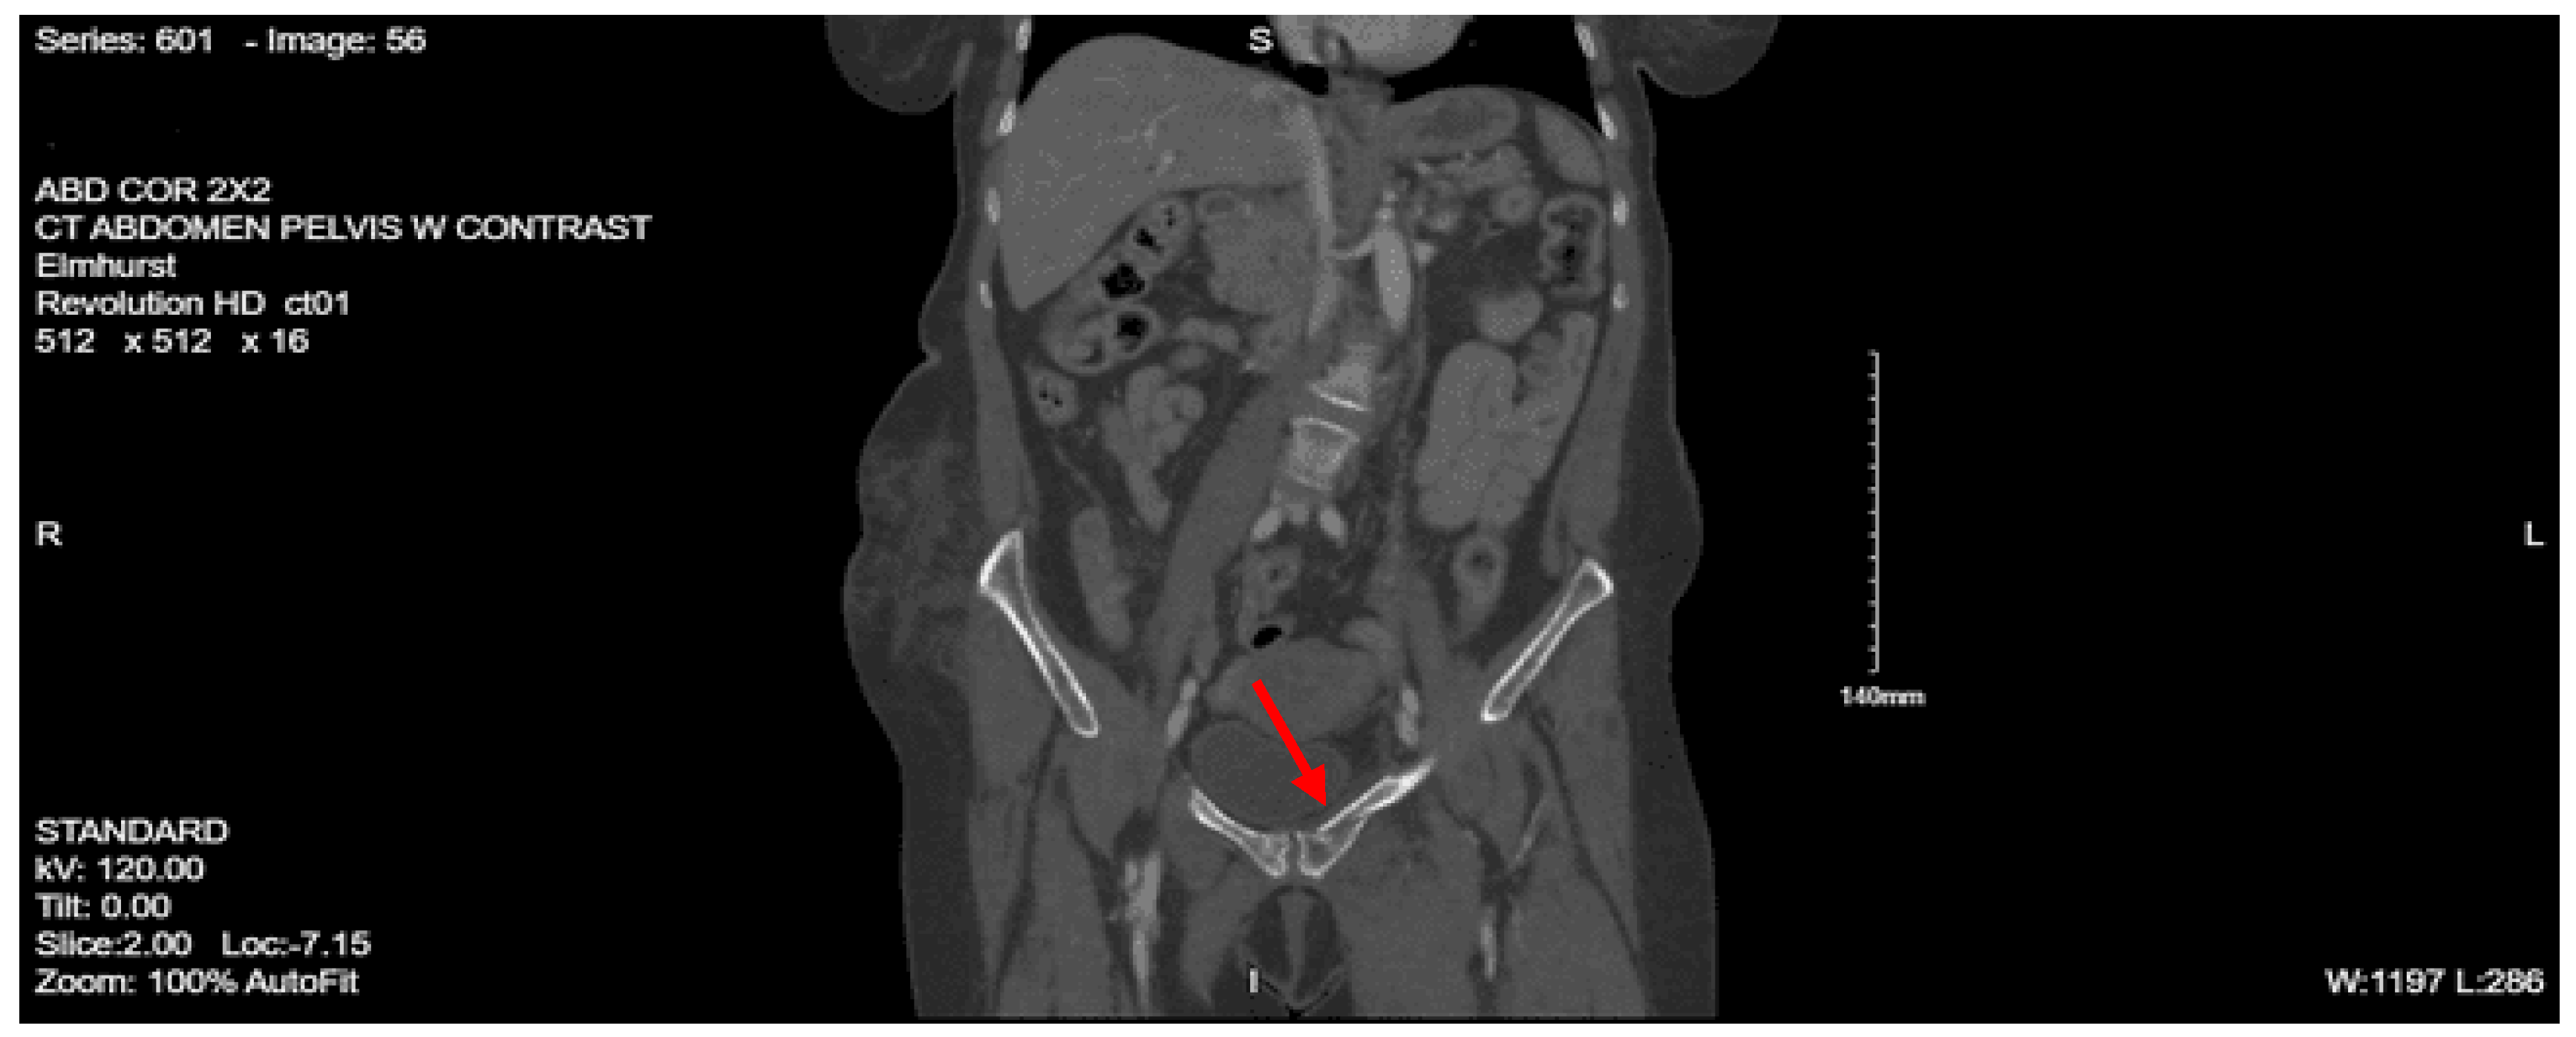

Imaging as shown in Figure 27, Figure 28 and Figure 29:

CT abdomen pelvis with contrast: There is retroperitoneal fluid surrounding the upper abdominal aorta without contrast blush. Linear flap within the upper abdominal aorta at the level of the celiac and SMA origins, concerning for traumatic injury. Lower thoracic findings include multiple posterolateral right rib fractures. Grade II hepatic injury. Periportal edema. Acute right L1 through L5 transverse process fractures. Acute right sacral ala fracture. Nondisplaced acute right inferior pubic ramus fracture. Nondisplaced acute fracture involving the lateral aspect of the right acetabulum.